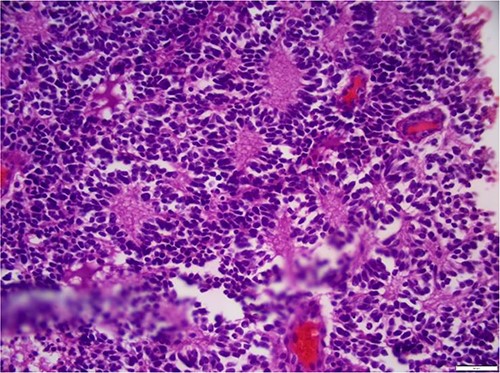

The laboratory examination’s results revealed a low hematocrit of 27 and a low hemoglobin (HB) of 8.5 mg/dl. Orbital ultrasonography revealed a hyper-echogenic tumor in the left eye with vitreous seeding (Fig. 2), while the orbital MRI showed a left intraocular mass of 10.10 mm by 8.7 mm with medium intensity in T1W/FLAIR sequences and a low intensity in T2W images (Fig. 3). The lesion has a slightly heterogeneous contrast enhancement in the post-contrast sequence with group D international classification of Rb (ICOF) stage I. The radiological findings most likely indicated Rb. Tumors occupied 50% of the globe, but there was no subretinal detachment. Fortunately, the tumor has not affected the optic nerve. An enucleation procedure (removal of the whole contents of the eye) under general anesthesia was performed (Fig. 4). Histopathological examination showed hyperchromatic small round blue cells with scant cytoplasm arranged in sheets, nests, and Flexner–Wintersteiner rosettes with histologic G3 with endophylitis, tumor necrosis, and calcification (35% of calcification is eosinophilic) that was consistent with Rb (Fig. 5). After 3 months of follow-up in the outpatient department, a prosthetic eye was implanted for cosmetic purposes (Fig. 6).

Hyperchromatic small round blue cells with scant cytoplasm arranged in sheets, nests, and Flexner–Wintersteiner rosettes.

Early detection of the disease while it is still within the eye is crucial for the successful treatment of RB [11]. Fortunately, we were able to diagnose Rb in our patient using orbital ultrasound and MRI. Obtaining efficient imaging and early intervention is challenging for the majority of patients residing in Africa. We were unable to save the child’s eyesight, but we successfully saved her life. The recommended course of action for managing this situation involves the surgical extraction of the eyeball. This treatment is referred to as enucleation. Following a successful surgery, we submit the specimen to the pathology lab for histological analysis. This analysis proved that the tumor was Rb. The specimen exhibited hyperchromatic, tiny, round blue cells with minimal cytoplasm, organized in sheets, nests, and Flexner-Wintersteiner rosettes. The histologic grade was G3, accompanied by endophytic growth, tumor necrosis, and calcification (35% of the calcification displayed eosinophilia). No invasion of the optic nerve or choroid was observed. The limitation of this instance is that we were unable to administer chemotherapy following enucleation due to the absence of an oncology facility and oncologist. After a 3-month period of monitoring, we proceeded to implant a prosthetic eye for cosmetic reasons.